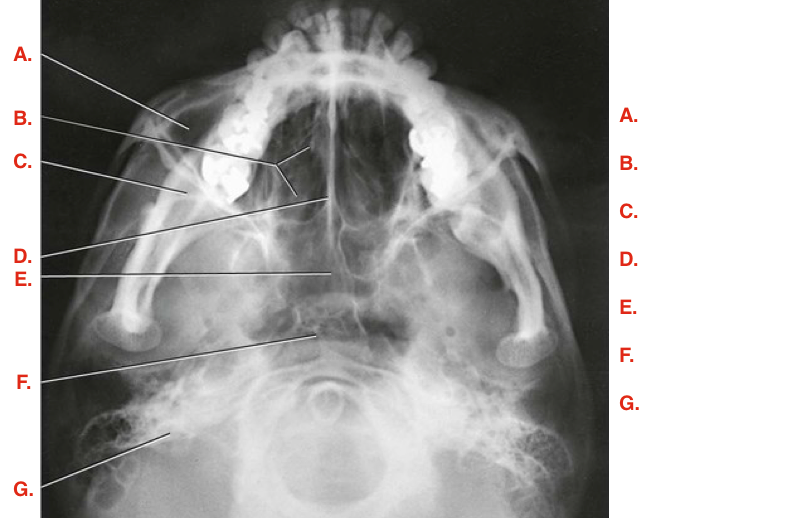

Question

Label the image

Image:

0f33fbaa-d4de-4cc8-88d6-768109148eb3 (image/png)

Answer

frontal sinuses

ethmoid sinuses

maxillary sinus

petrous ridge

mastoid air cells